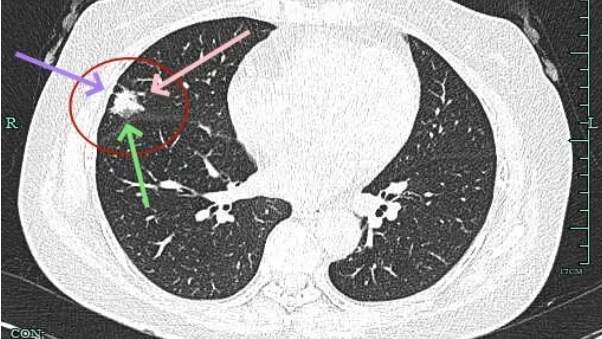

典型毛刺征,磨玻璃部分瘤肺边界清,表面不平,灶内密度不均。

实性成分占比高,表面不平,有细毛刺征,整体感觉有一定收缩力。